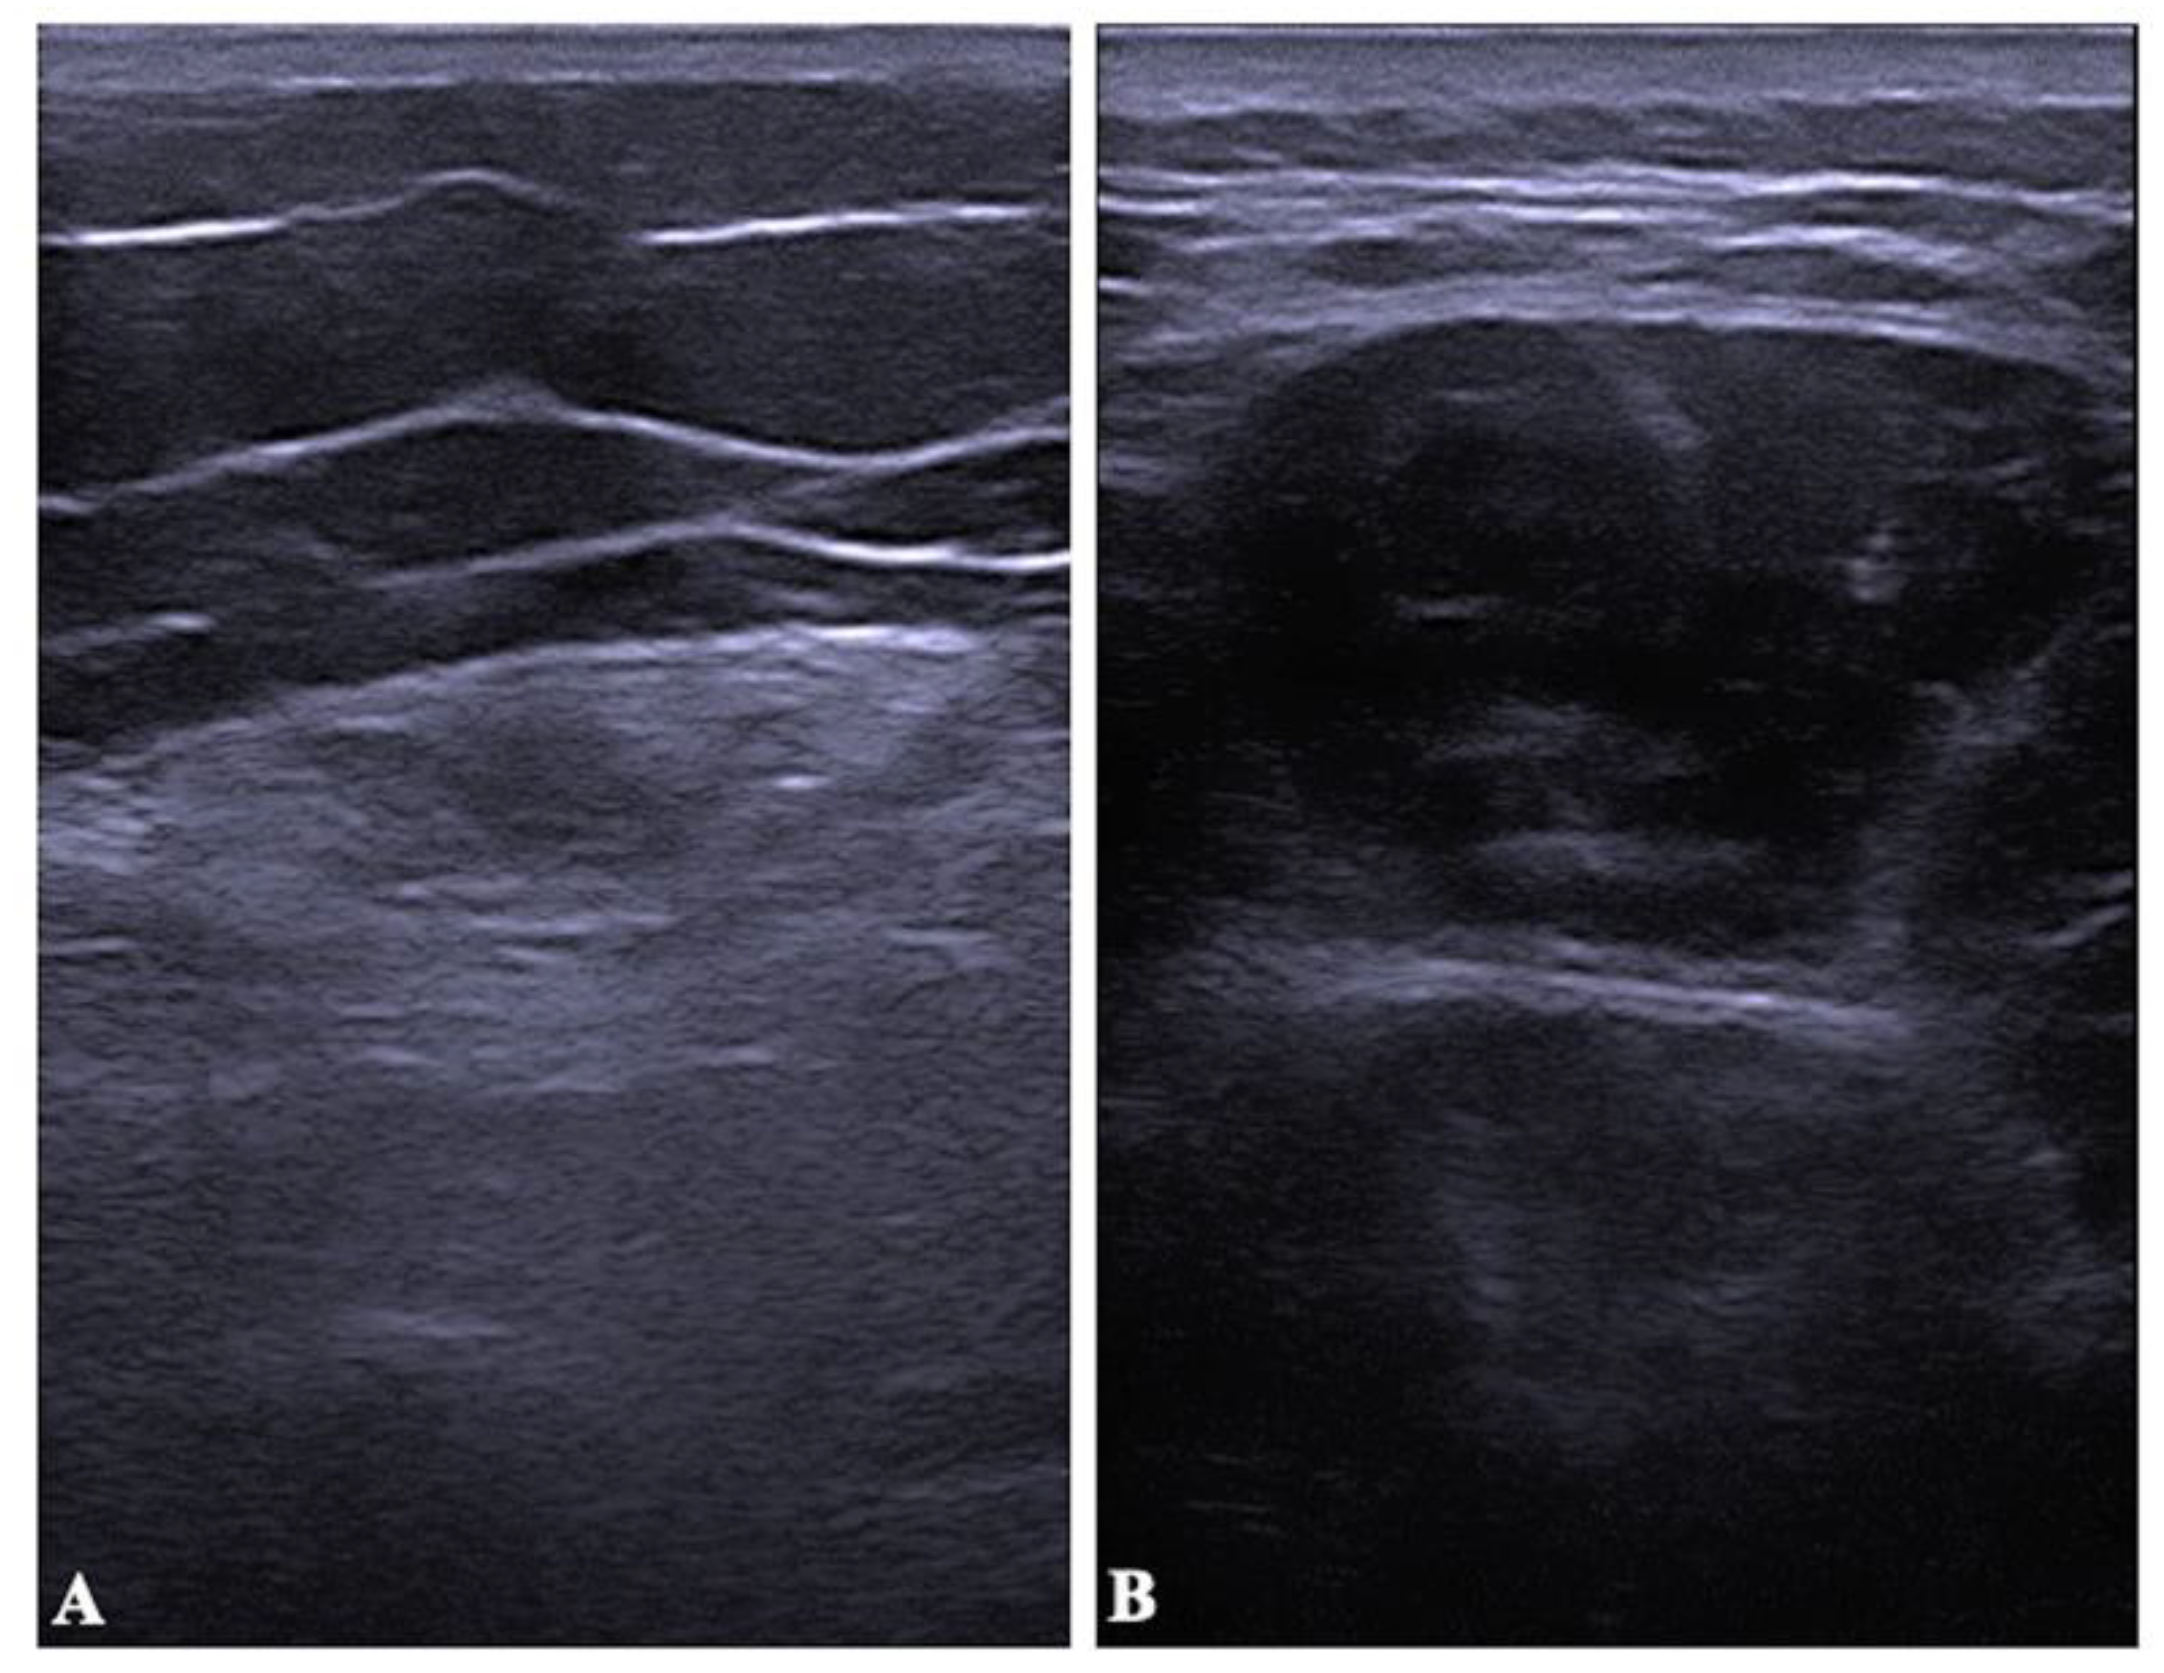

2.4. Muscle Thickness and Echo Intensity